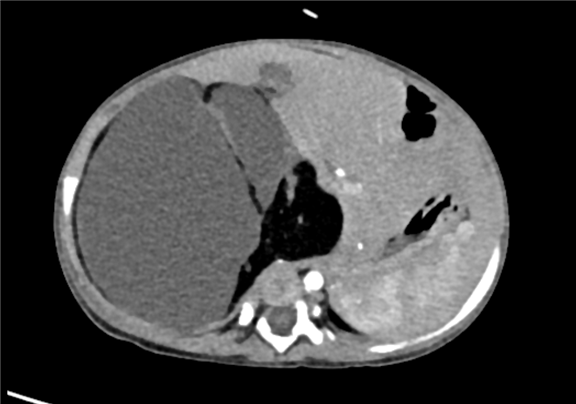

术前CT检查:

动脉期

上腹部增强CT:腹膜后巨大混杂密度肿块影,考虑畸胎瘤可能性较大